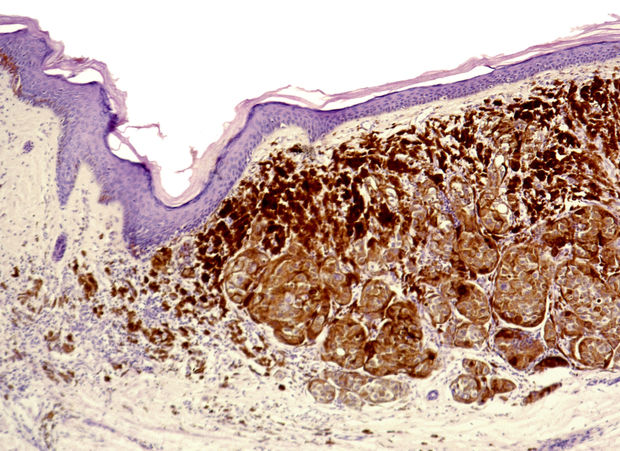

Combiner l'inhibition de BRAF et MEK dans le mélanome BRAF 600-Mutant

Dans cette étude - belge ! -, 25 patients atteints d'un mélanome avancé qui avaient précédemment reçu un inhibiteur MEK et un inhibiteur BRAF et dont la maladie avait progressé sur le traitement de l'inhibiteur BRAF ont été recrutés entre avril 2014 et février 2016 et traités avec dabrafenib à la dose de 150 mg par voie orale deux fois par jour plus trametinib à la dose de 2 mg par voie orale une fois par jour. Les patients devaient avoir arrêté le traitement par l'inhibiteur BRAF depuis ≥ 12 semaines. Tous les patients avaient reçu un traitement par immune checkpoint inhibitor après leur premier traitement par inhibiteur BRAF (avec ou sans traitement inhibiteur MEK). Le critère d'évaluation principal était la proportion de patients avec une réponse globale évaluée par l'investigateur.